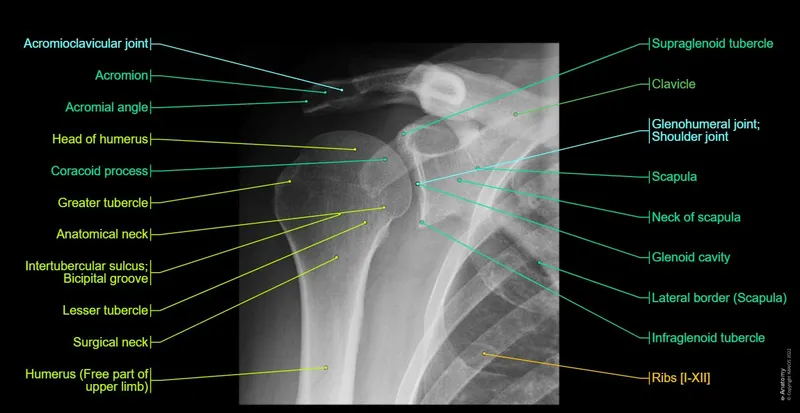

- Shoulder (AP View):

- Glenohumeral Joint: Normal space 4-5 mm.

- Acromioclavicular (AC) Joint: Normal space < 7 mm.

- Coracoclavicular Distance: Normal 11-13 mm.

- Greater Tuberosity: Lateral projection of humeral head.